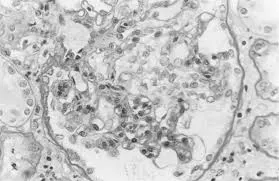

Doação renal em mulheres jovens pode impactar mais o feto do que a mãe — e esse dado muda o pré-operatório. O maior estudo já feito mostra aumento de PIG e sinais de disfunção placentária silenciosa, especialmente em nulíparas. Se você ainda não discute isso de forma explícita no consentimento, talvez esteja subestimando o risco.